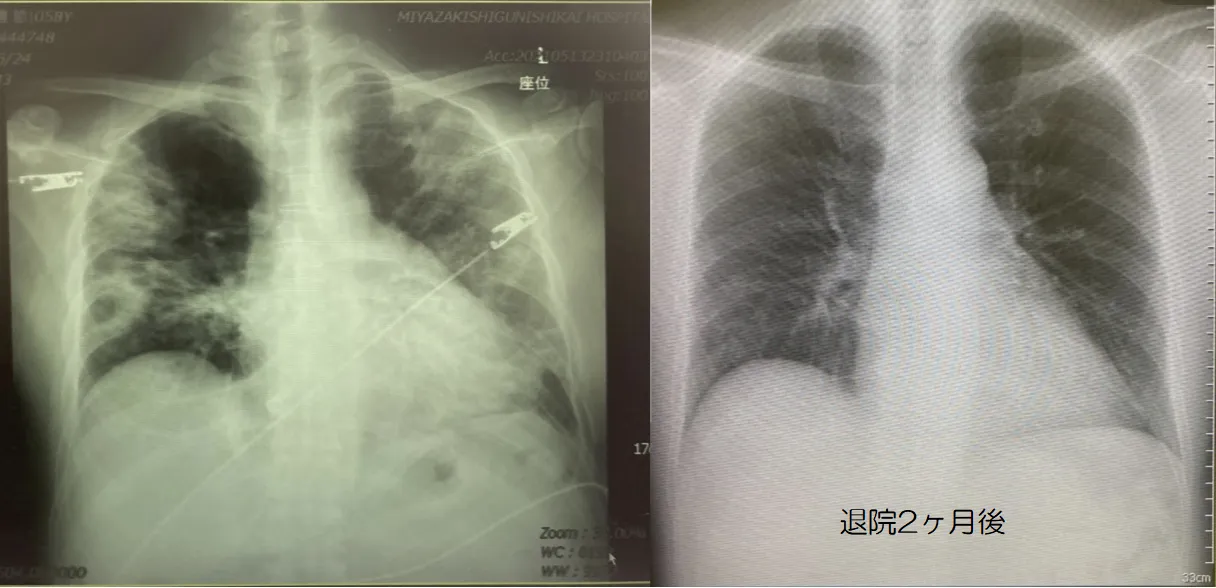

新型コロナ後の肺の状態